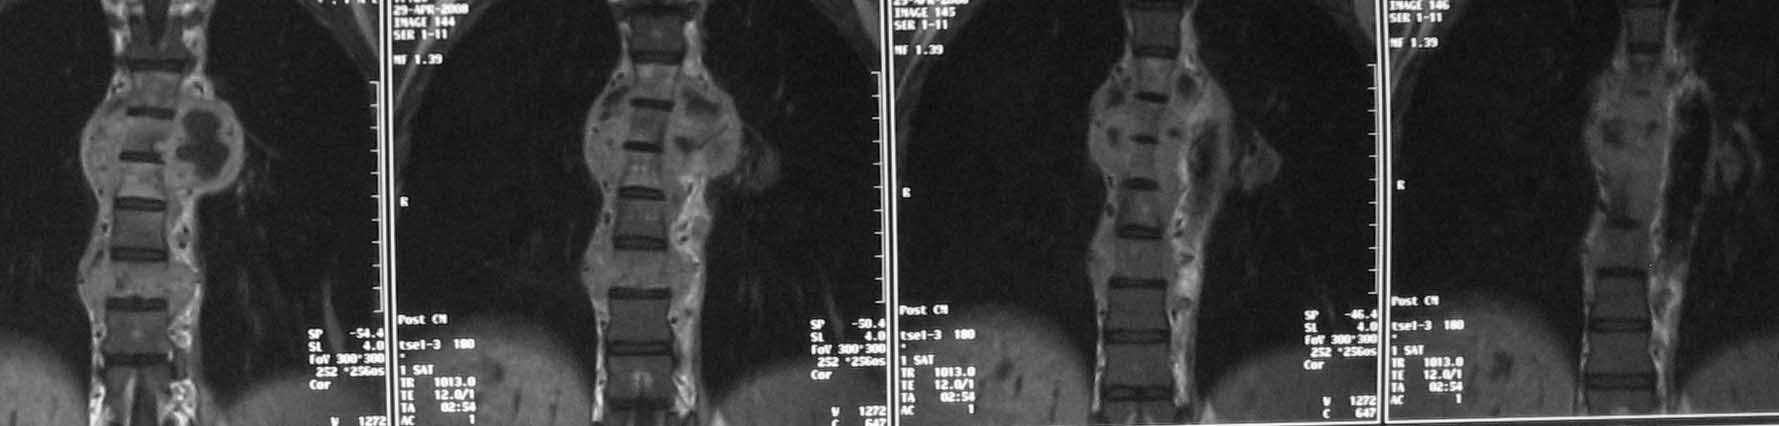

30-летняя женщина с болями в грудном отделе позвоночника в течение 3

месяцев получала консервативное лечение по поводу "остеохондроза".

Около 3 недель назад возникла резкая слабость в ногах, задержка стула

и мочеиспускания. КТ, МРТ, торакоскопичсекая биопсия с последующей

гистологией и посевом выявили хронический стафиллококковый

спондилодисцит. Клинически отмечается выраженный болевой синдром,

невозможность вертикализации пациентки из-за болей, нижний

спастический парапарез (до 3 баллов), стойкая задержка стула и

мочеиспускания. Соматически компенсирована. Стойкий субфебрилитет.

Лабораторные признаки воспаления выражены умеренно. Хотелось бы

услышать Ваше мнение, уважаемые коллеги, по поводу объема операции и

инструментации.